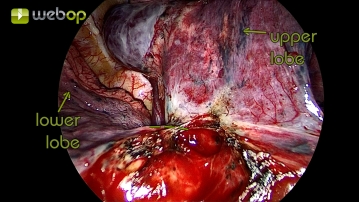

Dissektion der Parenchymbrücken zwischen Unter- und Mittellappen

Nach guter Darstellung der zentralen Pulmonalarterie können jetzt die verbliebenen Parenchymbrücken zwischen Unter- und Mittellappen entfernt werden. Bei hier nur schmal ausgeprägtem Lappenspalt erfolgt die Resektion mittels Bipolarklemme und Präparierschere.

- Die Parenchymbrücken könnten mittels Elektrokauter, Klammernahtgerät oder High Energy Device durchtrennt werden.